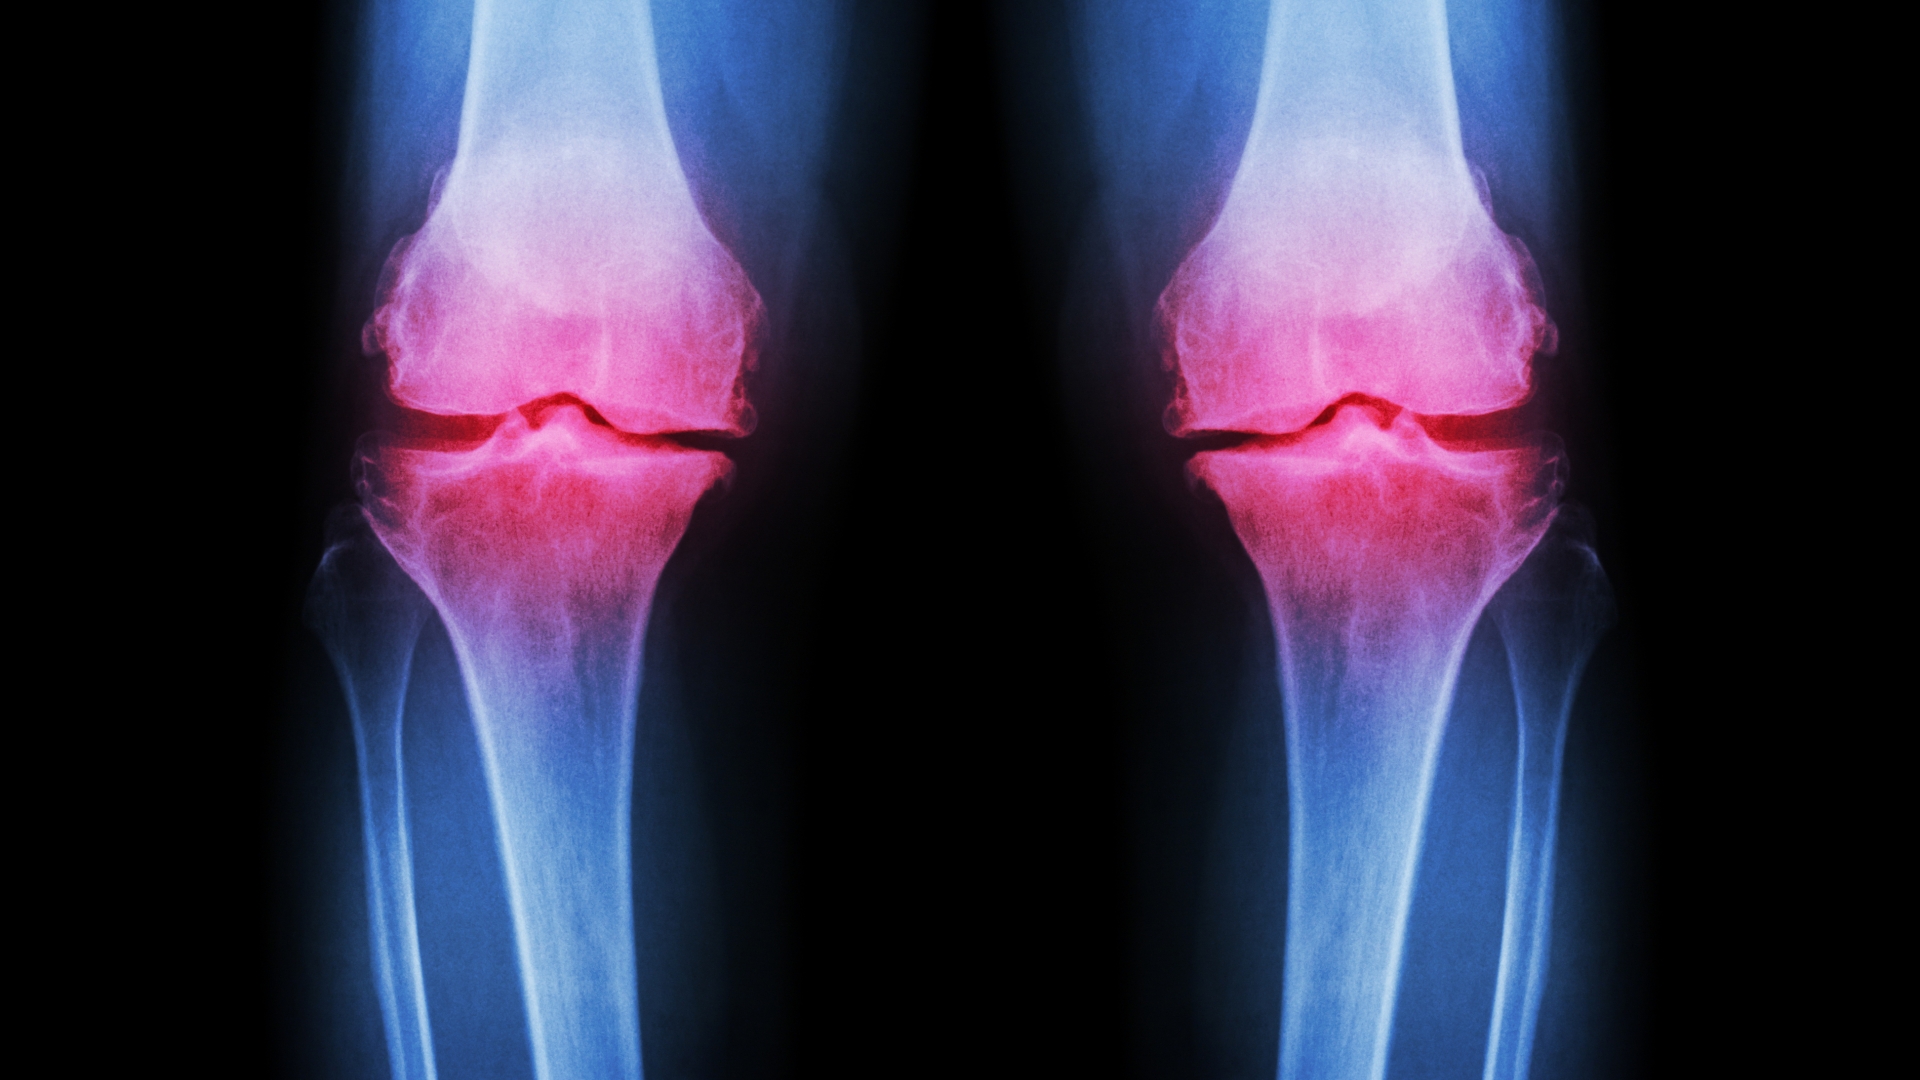

Arthrose an Knie-, Hüft- und Handgelenken ist ein häufiges Leiden im Alter - aber auch junge Menschen kann die Erkrankung treffen. Betroffene leiden unter fortschreitendem Knorpelverschleiß, der Schmerzen und Bewegungseinschränkungen zur Folge hat. Wie aber kommt dies zustande - und warum ist der Verlust des Knorpelgewebes so fatal? Wir klären auf.

Führen Knorpelschäden dazu, dass Gelenke ihren Dienst nicht mehr ordnungsgemäß versehen, kann dies zu schweren Bewegungseinschränkungen führen.

Wenn die Gelenke knirschen, schmerzen und sich nur schwer bewegen lassen, könnte eine Arthrose dahinterstecken: die weltweit häufigste aller Gelenkerkrankungen. Schätzungsweise 200 Millionen Menschen leiden an dieser Verschleißerscheinung, die durch den fortschreitenden Abbau von Knorpel gekennzeichnet ist - einem Gewebe, das zwar nur wenige Millimeter dick ist, aber eine wichtige Schutzfunktion erfüllt.

Durch Alterungsprozesse, Verletzungen oder anhaltende Überbelastungen - zum Beispiel durch starkes Übergewicht - kann die schützende Knorpelschicht allerdings Schaden nehmen und sogar ganz verschwinden. Dadurch entstehen mit der Zeit auch Schäden am Knochen. Am häufigsten sind Hände, Knie und Hüften davon betroffen. Prinzipiell kann jedoch jedes Gelenk eine Arthrose entwickeln.